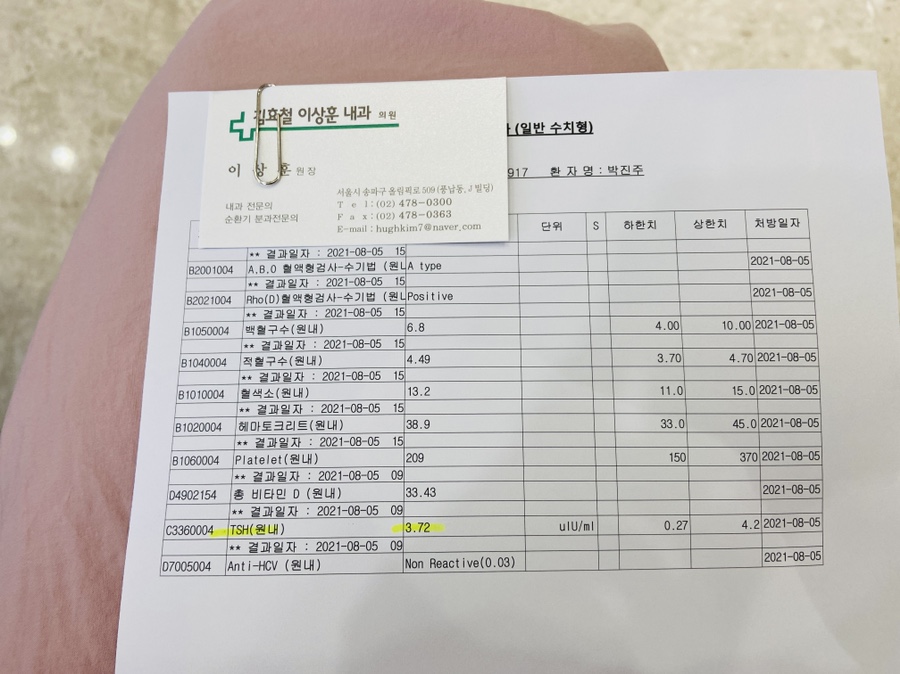

송파 마리아는 12주 1차 기형아 검사 전에… 8주 됐을 때 검사를 해요

혈액검사와 소변검사를 하고 집으로 돌아왔습니다.

아침 일찍 마리아 갔다 왔는데… 마리아는 2시간 정도 지났을 때 전화가 왔어요 ㅜㅜ

피검사 결과가 일부 나왔는데 갑상선 수치가 애매하다고 ㅜㅜ내과에 다녀오시는게 좋겠다고…검사 결과를 받으러 병원에 오실 수 있냐고 말씀을 하셨어요. ㅠㅠ일반인의 기준은 4를 넘으면 안 되는데 임산부의 경우 그 기준이 더 타이트하면 수치가 3.72면 높은 편이라고….

집에서 좀 쉬었다가 마리아를 다시 방문하겠어요.검사 결과를 받고 나서 추천할 만한 내과 명함을 받았습니다.

TSH 수치랑 다른 수치 몇 개 보는 거야 피 몇 통 뽑고 왔어요 ㅜㅜ

어쨌든 TSH 갑상선 자극 호르몬 수치 때문에 제가 걱정을 많이 했고, 그래서 남편이 최근에 논문을 찾아주면서 수치는 괜찮다고 계속 안심시켜줬어요.ㅜㅜ 고마워요. ㅜㅜ